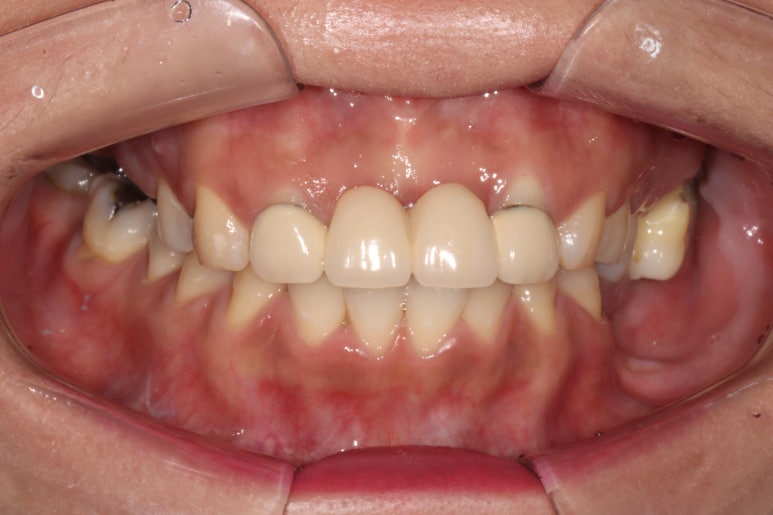

Before & After

좌측이 치료 전, 우측이 치료 후 정면 사진입니다.

솔직히 이제 치료를 받은 곳이 있으신가? 싶을 정도로 깔끔하게 마무리가 잘 된 것 같아요.

예쁜 앞니 지르코니아 크라운 제작은 저희 치과의 자랑입니다! 정말 색깔 잘 나왔네요~